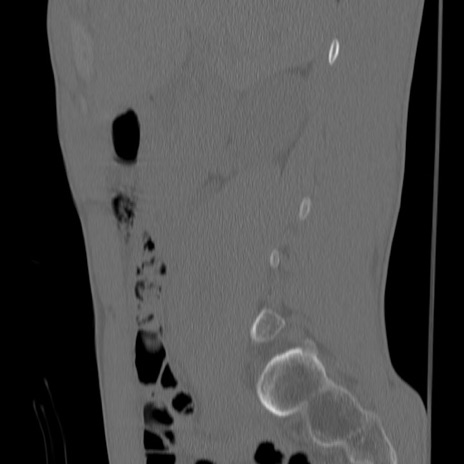

症例3 腰椎CT(矢状断像)

【症例】30歳代男性

【主訴】腰痛

【現病歴】本日旅行先で観光中に、友人と衝突し転倒し受傷。

【身体所見】麻痺なし、右下腿内側前面外側、左下腿内側に知覚鈍麻・しびれ

異常所見と診断は?

腰椎CT